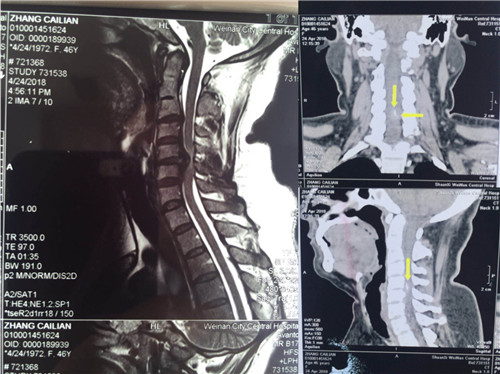

术后

尽管术中操作空间狭小,暴露不是那么充分,但经过细致耐心的剥离显露,小心谨慎的操作,最终顺利于5月4日完成了此例高难度手术,摘除了游离的蜕变髓核,切除了创伤后形成的机化瘢痕,实现了椎管容积的恢复、脊髓的减压,完成了融合器的植入,前路钢板螺钉的固定。术后患者症状改善明显,左侧肢体麻木,活动不灵便现象显著减轻,目前已经在支具的保护下下地活动。